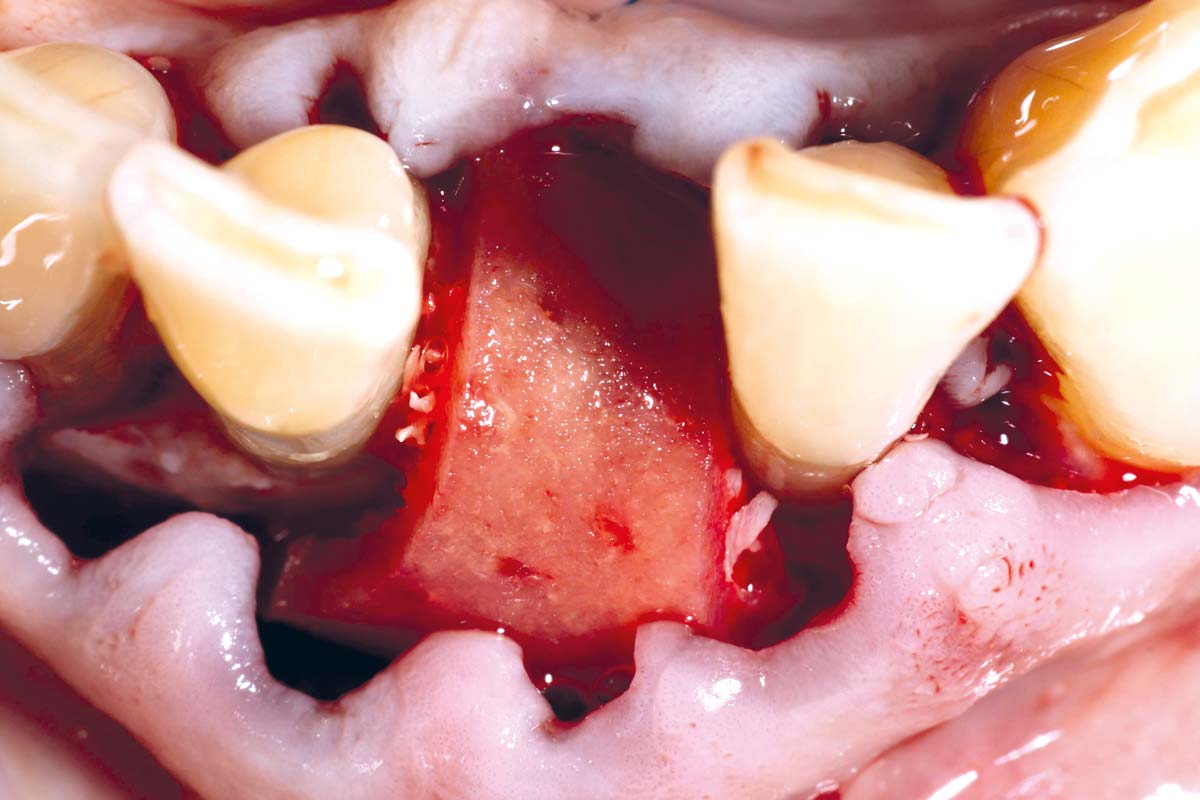

Pre-operative situation showing tooth 21 with deep periodontal pocket. Tooth presented with mobility grade III.